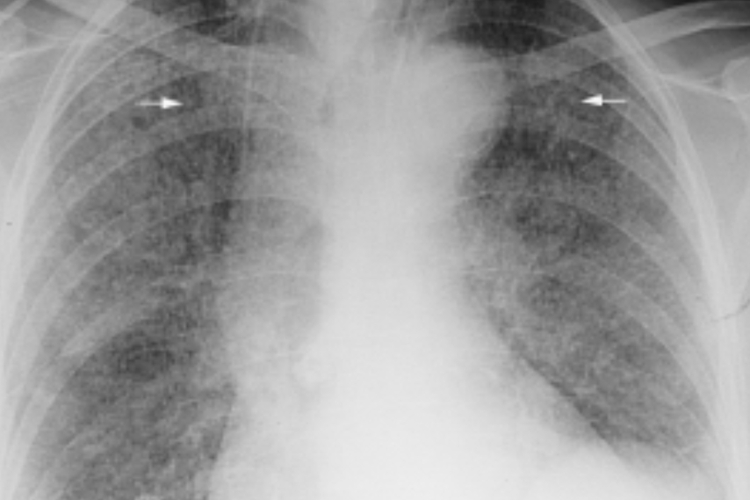

急性血行播散型肺结核表现为两肺弥漫分布的粟粒状影,粟粒大小为1-3mm,边缘较清晰。典型表现为“三均匀”,即分布均匀、大小均匀和密度均匀。